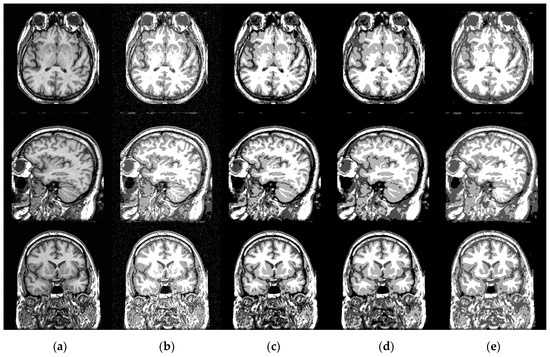

4.2. Capability of Estimating the Bias Field